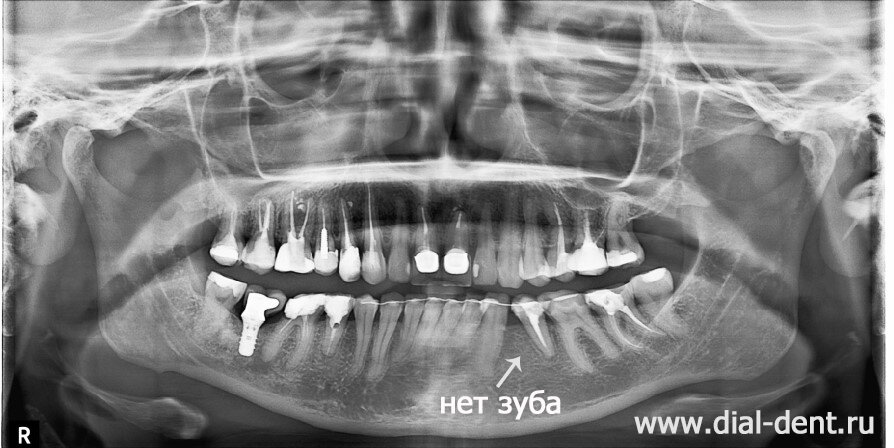

Молодая женщина обратилась к специалистам Семейного стоматологического центра "Диал-Дент". Так как пациентка хотела изменить эстетику зубов, она сначала пришла на консультацию к стоматологу-ортопеду, который устанавливает коронки и виниры на зубы. В ходе диагностики выяснилось, что у пациентки отсутствует один жевательный зуб на нижней челюсти. Ране пациентка проходила ортодонтическое лечение в другой клинике, но результатом не довольна - зубы сдвинули, закрыв щель от отсутствующего зуба, но красоты не добились. Задачей данного лечения было: Ортодонтическое лечение с нейромышечной подготовкой и остеопатической коррекцией Ортодонтическое лечение начинается с нейромышечного этапа и заключается в возвращении нижней челюсти в правильное положение, которое утрачено в результате нарушений прикуса из-за отсутствующего зуба и неправильного пломбирования жевательных зубов, понизившего прикус. Высоту прикуса нейромышечный стоматолог подобрал с помощью компьютерного миографа. По результатам компь

Молодая женщина обратилась к специалистам Семейного стоматологического центра "Диал-Дент". Так как пациентка хотела изменить эстетику зубов, она сначала пришла на консультацию к стоматологу-ортопеду, который устанавливает коронки и виниры на зубы. В ходе диагностики выяснилось, что у пациентки отсутствует один жевательный зуб на нижней челюсти. Ране пациентка проходила ортодонтическое лечение в другой клинике, но результатом не довольна - зубы сдвинули, закрыв щель от отсутствующего зуба, но красоты не добились.

место отсутствующего зуба закрыли, сдвинув соседние зубы